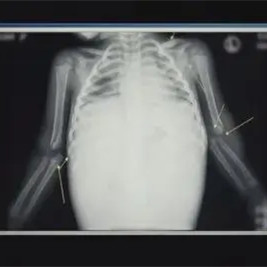

20年的十月中旬, 韩国一家医院收到了一位情况特殊的只有16个月大小的病人,被送到医院的时候惨不忍睹,完全不像是一个正常的婴儿,在抢救 的过程中心脏3次停止了跳动,医生拼尽全力最后也没有从死神手里把这个年轻的小生命抢救回来 。16个月的小郑仁去世了,医生在检查郑仁遗体的时候,发现这个 一岁多的小女孩竟然只有17斤重量,但是小女孩的腹部隆起得非常吓人,在医生仔细的检查后发现,腹腔大出血是导致郑仁死亡的根本原因,这个才16个月的小孩,腹腔出血量竟然高达6000ml,6000ml的出血量相当于郑仁全身血液的百分之80。

郑仁的身上 随处可见淤青和疤痕,甚至还没伤口没有完全愈合的结痂。全身多处骨折,有新骨折、旧骨折、甚至还有曾经骨折养好又骨折的地方,经过医生大概的计算,郑仁的双腿双臂,肋骨锁骨,总之郑仁的身体上面除了脊椎是好的之外 ,其他没有一个完好的地方。就算是大鹏神仙转世都救不活这个小女孩 。

那么到时大出血的原因是什么呢,郑仁的胰腺破裂导致腹腔出血,同时就连郑仁的小肠肠系膜也都破裂了。医生还发现,郑仁的腹腔都已腐烂了,这个发现证明了, 郑仁的脾脏破裂绝对不是这几天发生的事情。那么为什么郑仁在快要死亡的时候才被送过来抢救呢?